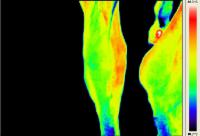

Rasmus - Pferd mit Arthrose - Horse with Osteoarthritis![]() Walzertraum - Pferd nach Sehnen-OP - Horse after tendon operation